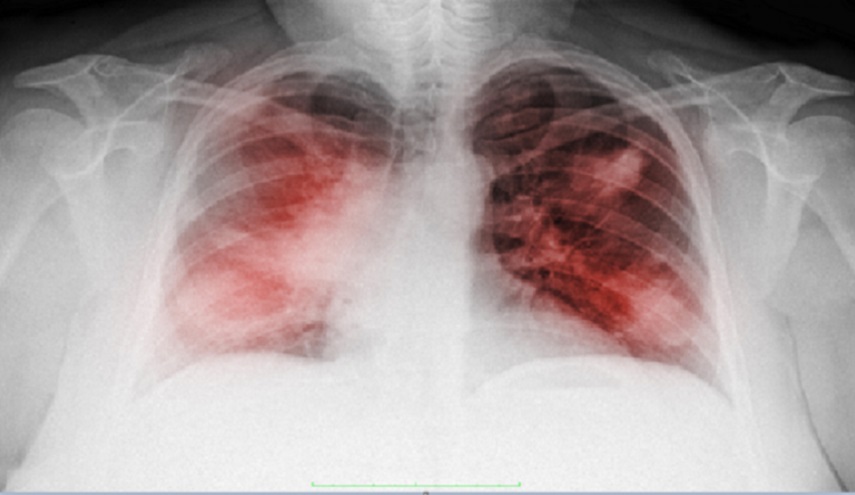

الصحة_الكوثر: أعلن إيفان كاراسيف، أخصائي طب وجراحة الأورام، أن أعراض الالتهاب الرئوي عند الإصابة بـ "كوفيد-19" وسرطان الرئة تتطابق جزئيا، لذلك من السهل الخلط بينها.

وقال الأخصائي في حديث لصحيفة "روسيسكايا غازيتا"، لا تظهر أعراض "كوفيد-19" لدى مرضى السرطان بصورة واضحة، لأن المصاب بسرطان الرئة ، يعاني أيضا من السعال والبلغم وصعوبة التنفس.

وأضاف، مرضى السرطان أكثر عرضة من الآخرين لخطر الإصابة بالشكل الحاد من "كوفيد-19"، وخاصة الذين شخصت إصابتهم بالسرطان لأول مرة وكذلك الذين تم علاجهم من سرطان الرئة.

وقال، تشمل المضاعفات الصعبة، التهابا رئويا ثنائي الجانب (يلاحظ في 75% من الحالات)، ومتلازمة الضائقة التنفسية الحادة (17%) و متلازمة خلل وظيفة الأعضاء المتعدد (11%).